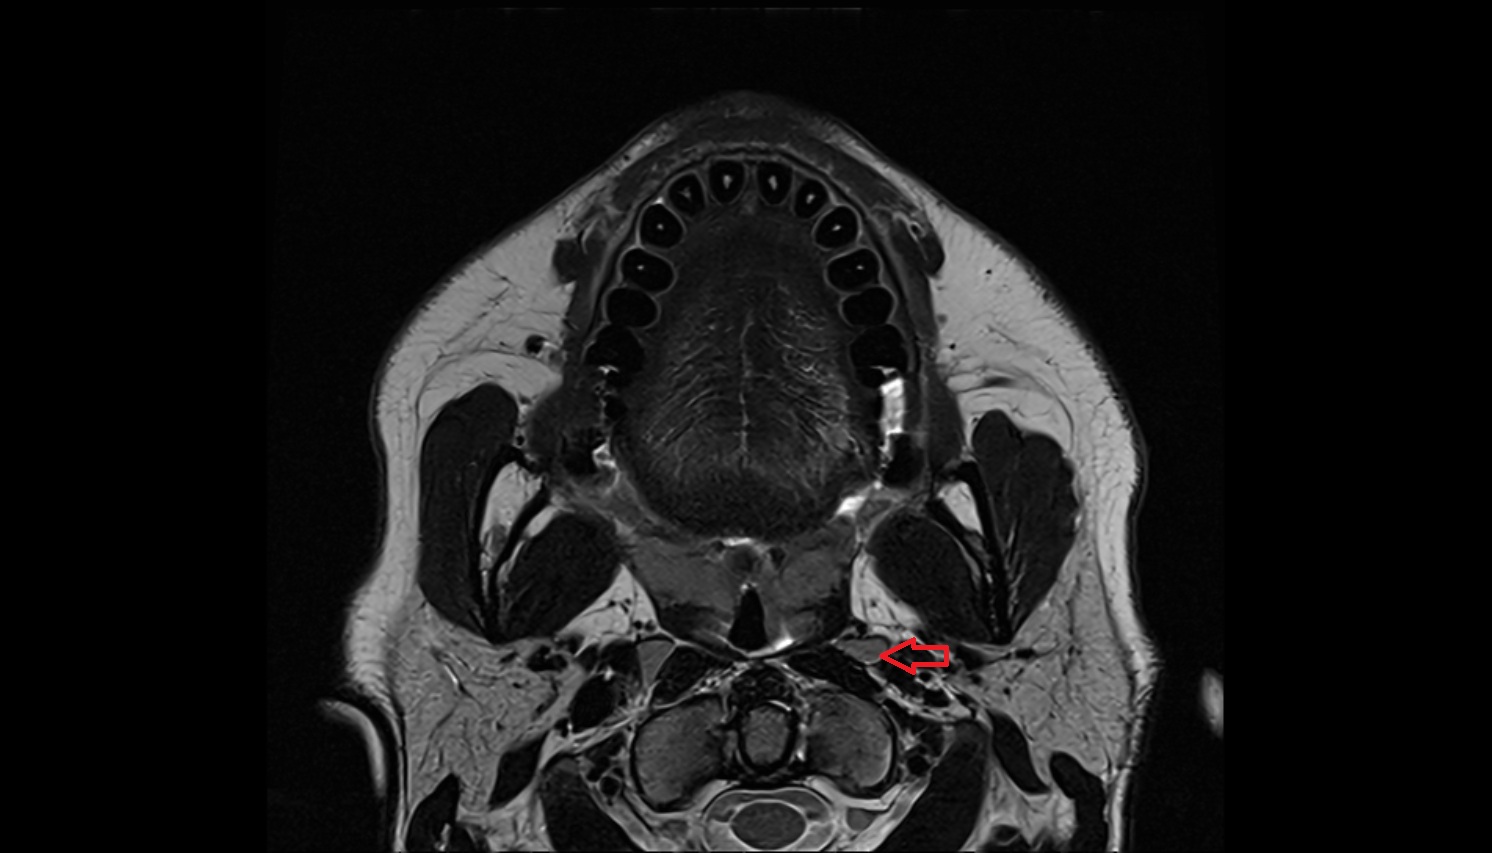

- Peripheral zone of prostate

- Anterior Fibromuscular Stroma of prostate

- Central zone of prostate

- Transitional zone of prostate